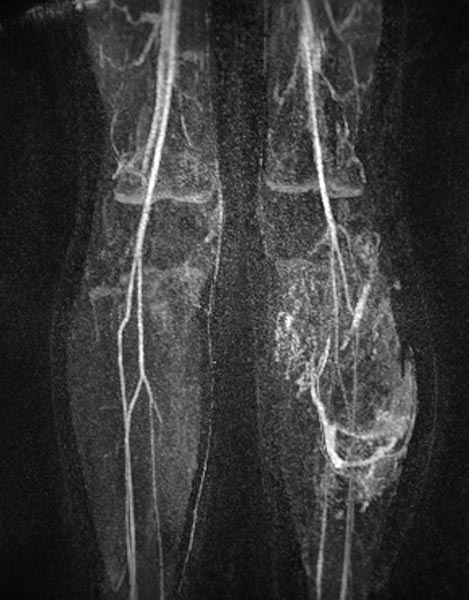

Contrast-enhanced MR angiography (MIP) shows complete enhancement of the venous malformation component in the left calf with contrast pooling.